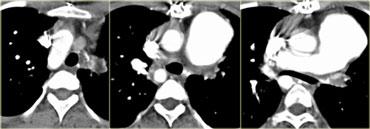

On the left a sagittal scanogram, axial image and sagittal reconstruction of a 5 year old girl with noisy breathing and occasional episodes of cyanosis.

First look at the images then continue.

The findings are:

- anterior compression of the trachea

- brachiocephalic (innominate) artery is located more to the left and compresses the trachea

The diagnosis is the innominate artery compression syndrome.

In infants the innominate artery arises more to the left than in adults, so it’s got to go in front of the trachea.

It may compress the trachea, leading to stridor, cough and dyspnea.

This compression decreases with age and these patients will outgrow it.

The compression in the innominate artery compression syndrome is located on the right anterior side and at the level of the thoracic inlet.

This is much higher than in the double arch or Right Aortic Arch with Aberrant left subclavian

On the left another case with mild compression on the trachea.